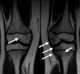

Osteonecrosis of the distal tibial epiphysis

Osteochondritis dissecans (OCD or OD) is a joint disorder primarily of the subchondral bone in which cracks form in the articular cartilage and the underlying subchondral bone. OCD usually causes pain during and after sports. [Source: Wikipedia ]